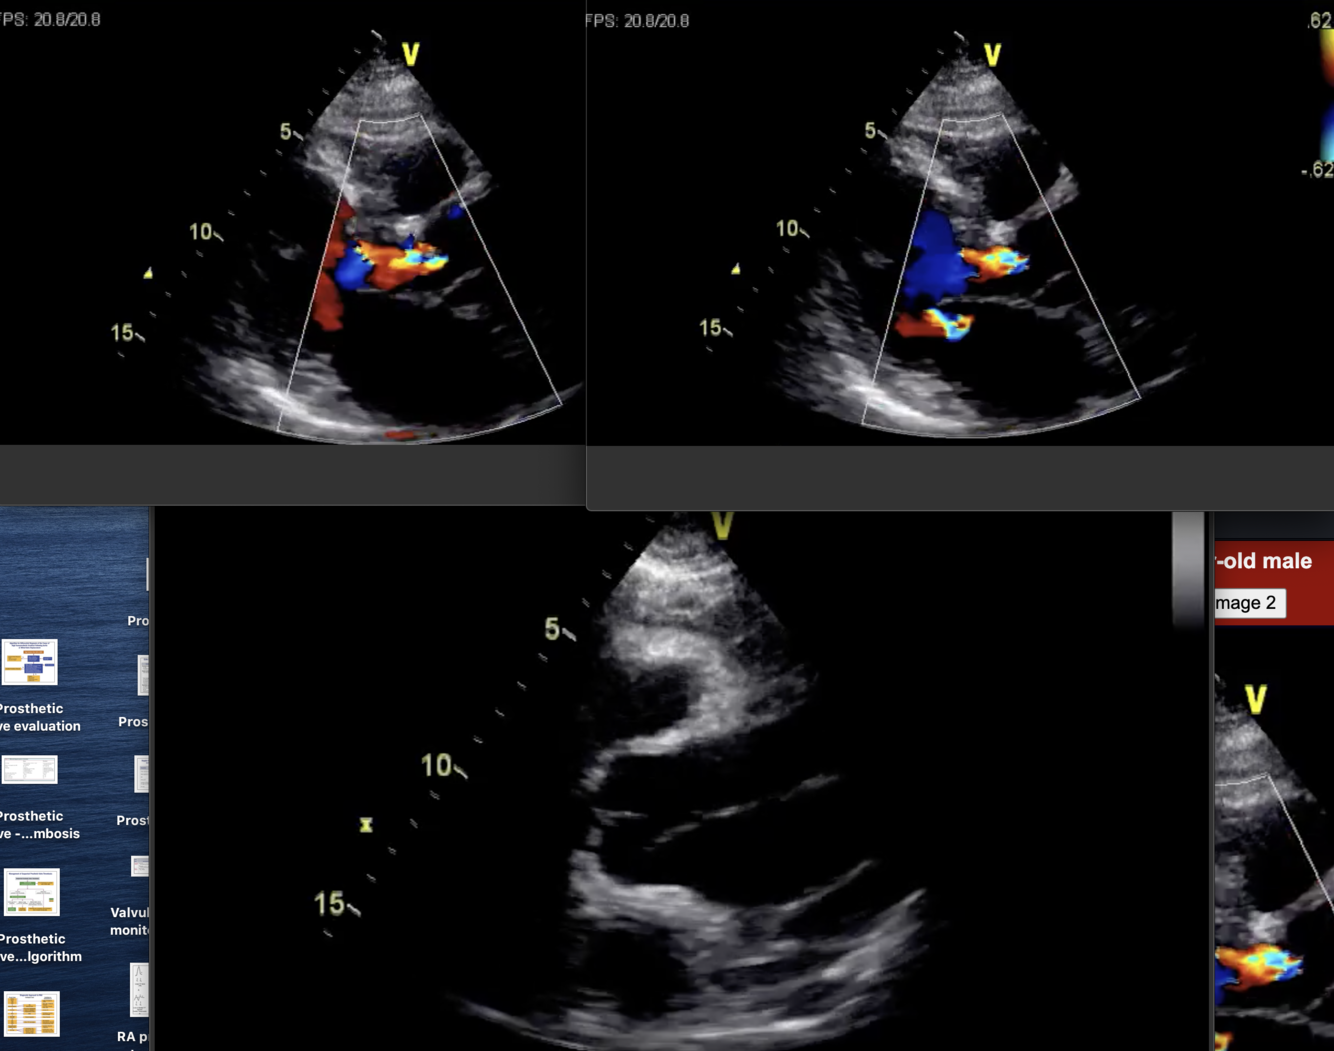

Describe the findings: